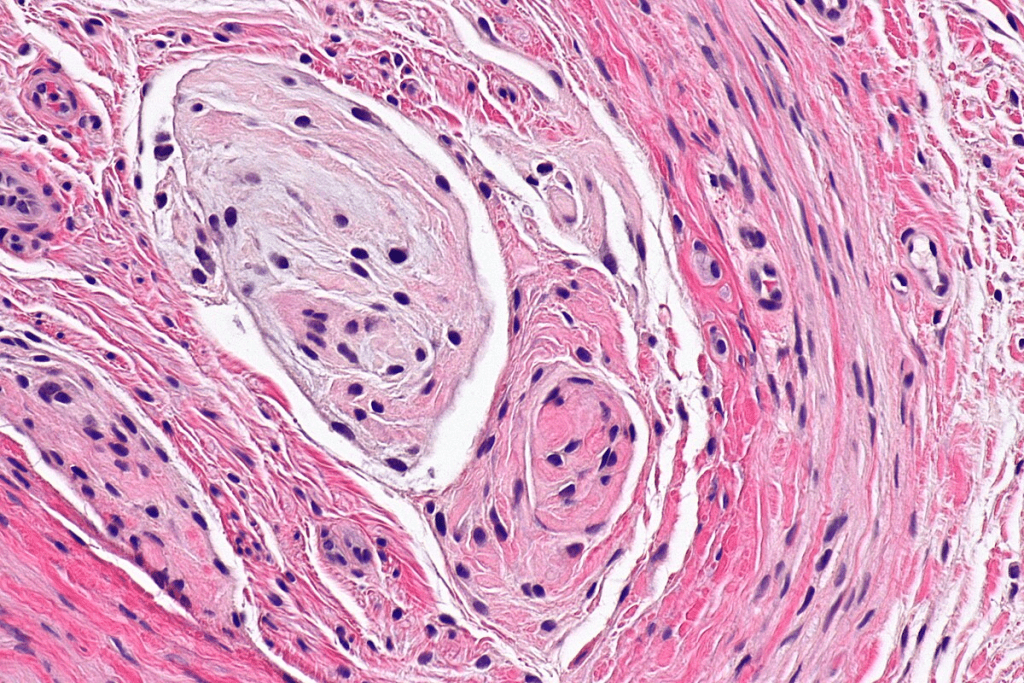

Vascular Structure Abnormalities

GI AVMs have abnormal connections between arteries and veins in the gastrointestinal tract. These vascular malformations can cause serious health problems. Issues include bleeding and other complications.

The abnormal vascular structure is thought to result from several factors. These include vascular degeneration and increased venous pressure.